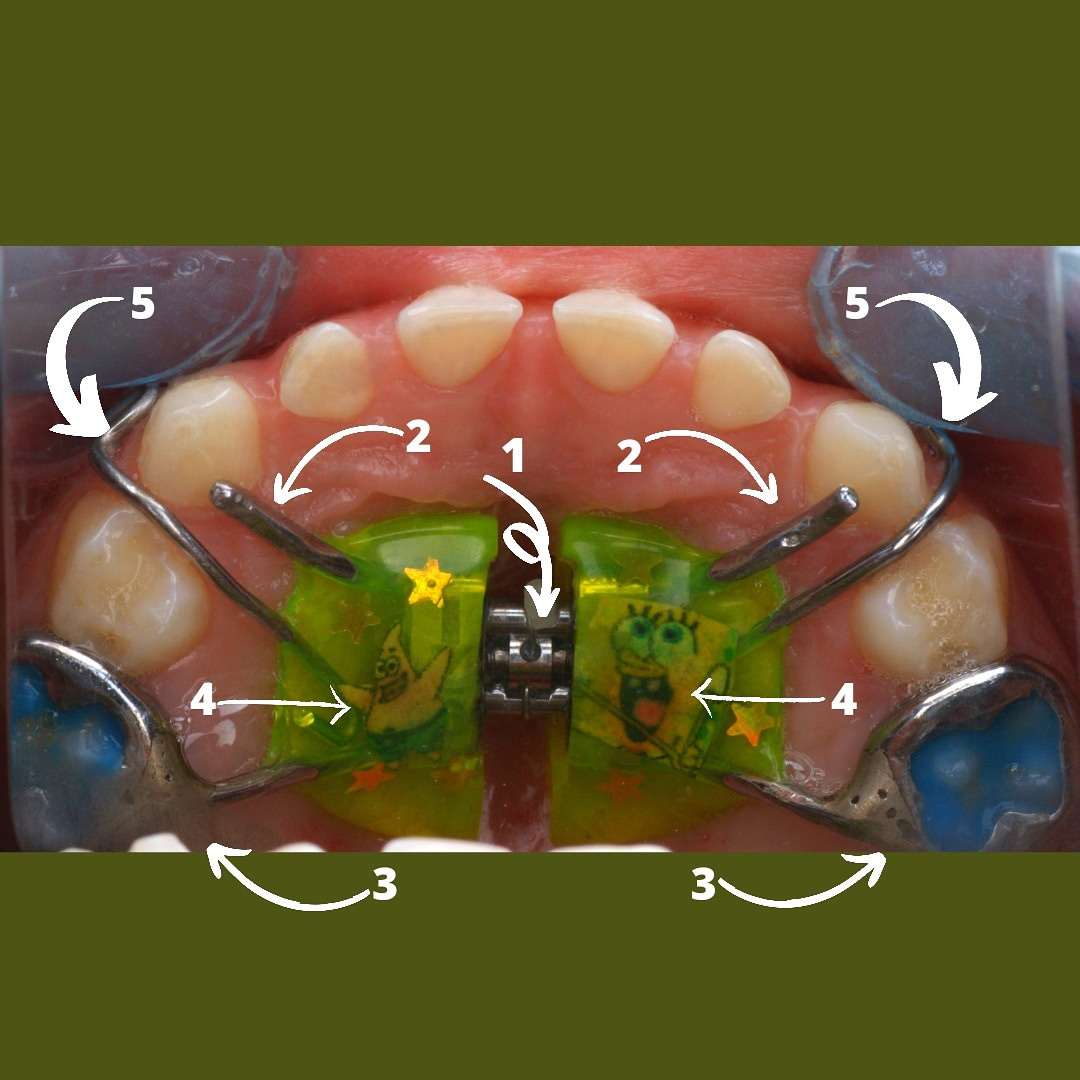

КОНСТРУКЦИЯ АППАРАТА МАРКО РОСА

1️⃣ ВИНТ ХАЙРЕКС. Создаёт расширяющее усилие.

2️⃣ МЕТАЛЛИЧЕСКИЕ ЛАПКИ. Это дополнительные элементы фиксации, которые упираются в молочные клыки, создают точки приложения силы к зубному ряду.

3️⃣ КОЛЬЦА НА МОЛОЧНЫЕ МОЛЯРЫ. Обеспечивают фиксацию аппарата на опорных зубах с помощью специального стоматологического клея.

4️⃣ ПЛАСТМАССОВЫЙ БАЗИС (пластинка). Объединяет все элементы в единую систему и передаёт расширяющее усилие винта на нёбо.

5️⃣ ДОПОЛНИТЕЛЬНЫЕ ЭЛЕМЕНТЫ (крючки для лицевой маски)

*️⃣ Спанч Боб и Патрик😀

Аппарат Марко Роса (Marco Rosa) - маленький невидимый помощник в больших ортодонтических делах💗